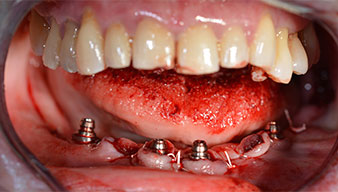

A three-dimensional cone beam computed tomography scan (CBCT, Planmeca) was performed to aid planning and minimize risks. This revealed that the quality and quantity of the available bone were sufficient for the surgery and immediate restoration using the Fast & Fixed method. Following the protocol for this concept, the implants are inserted at 35, 32, 42 and 45. Angling the distal implants by up to 45° shifts the emergence profile to posterior and generates a larger support polygon (Fig. 3).

Fig. 3

Angled abutments (35°) were screwed in to compensate for the divergence of the distal implants, with the result that the emergence profile of all implants was as perpendicular as possible to the bite plane. This is a prerequisite for occlusal placement of the provisional and subsequently the permanent denture (Fig. 15 and 16).

Implants

Fig. 15

Fig. 16